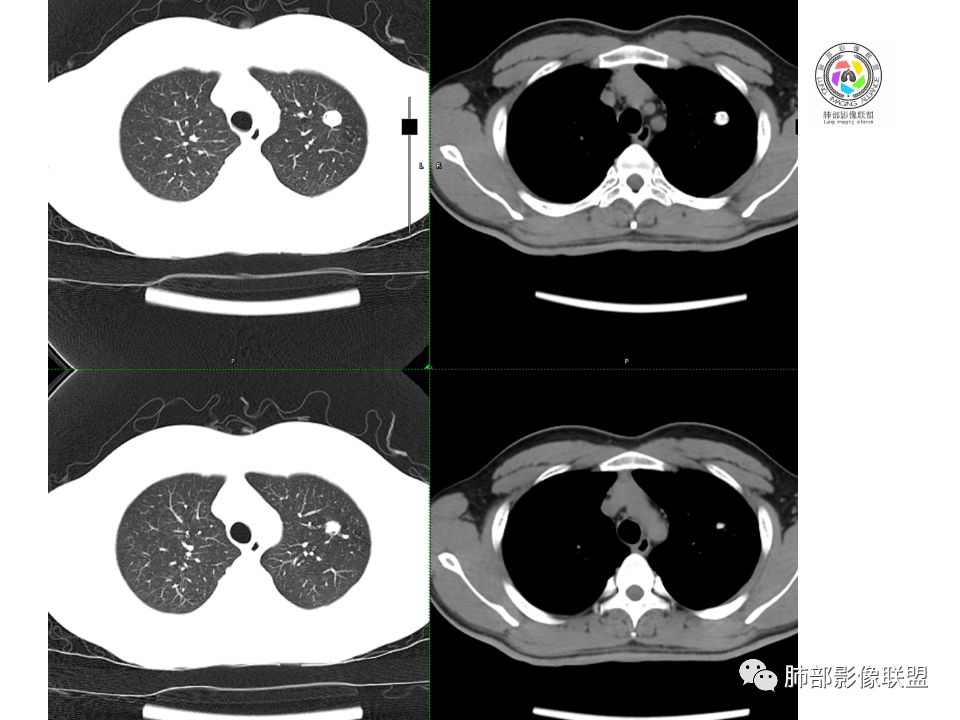

晨读:前纵隔占位,密度不均,沿着右侧纵膈延伸到肺门水平,周围支气管推移,大血管向内推移。临床有重症肌无力,考虑胸腺瘤可能,鉴别淋巴瘤。

患者青年人,前纵隔占位,无增强,猜一个淋巴瘤,不知道右下肺膨胀不全原因是什么

右前纵膈肿块,偏一侧生长,形态欠规则,密度不均匀,其内可见小点状钙化,双肺多发小叶中心结节及钙化灶,右侧胸膜增厚(有陈旧性结核可能),青年男性(27岁),没有增强,考虑,1,前纵隔生殖细胞瘤2,精源细胞瘤

右前上纵隔占位,瘤肺交界面清楚,提示纵隔来源,其内有点状钙化,右侧胸腔积液,有临床症状,年龄轻,考虑生殖来源可能,胸腺瘤待排,请结合临床相关检查或CT增强进一步检查。

前纵隔占位,伴点状钙化;上腔静脉后移位。伴右胸膜局限性增厚,临床有重症肌无力,病人年轻,考虑胸腺瘤可能,鉴别生殖源性肿瘤。

临床症状眼睑下垂,右纵膈占位,偏向一侧,有分叶,跟上腔静脉边界不清,淋巴结肿大,考虑胸腺瘤或胸腺癌

右前纵隔占位,有分隔`低密度、点状钙化,边缘光滑,侵袭心包不明确,伴右胸少量积水,考虑恶性,生殖源性可能大,有视物不清,是否脑转移待查。建议HCG丶AFP检查。鉴别1:胸腺瘤、癌,30一40岁以下,少见,但有眼脸下垂,肌无力,待排除。2:淋巴瘤:侵袭性不强,有点状钙化,不支持。3:畸胎瘤:有低密度丶钙化,建议增强进一步明确。4:神经源性:一般后纵隔常见,不支持。5:LCD:症状少见,可以有树枝状钙化,浆细胞型可以有低密度,增强进一步明确

前纵隔偏侧肿块,病灶内见点状钙化,症状肌无力,考虑恶性,胸腺瘤或神经内分泌癌

没有增强,好像两个病灶,上方三角形的像是胸腺增生。下方肿块,没有增强显得更难了,微钙化,轻度分叶,像有坏死低密度影,右侧少量胸水,胸膜受侵.,有视物模糊眼睑下垂。考虑胸腺瘤B1型及以上、B2型可能或生殖细胞瘤

患者年轻,有肌无力症状,除肿块外,前纵隔密度增高,与心包界限不清,考虑恶性。

前纵隔右区占位性病变,上区与胸腺延续,下区呈分叶状,尽管年龄<30还是首先考虑胸腺瘤,侵袭性可能性大(眼睑下垂不知是否有关)。鉴别主要是生殖细胞类肿瘤,主要是精原细胞瘤。另左肺上叶结核球,右侧胸腔积液,需除外结核性胸膜炎和转移

前纵隔占位性病变,偏向一侧生长,密度不均,可见点状钙化,考虑胸腺瘤,鉴别精原细胞瘤

右前纵隔肿块,边界清楚,密度欠均匀,内似有分隔和低密度区,似有多结节融合,几乎从上到下,年龄较轻,不是胸腺瘤好发年龄,但却有视物模糊,眼睑下垂症状,考虑淋巴瘤?鉴别胸腺瘤?结核?

右前上纵膈肿块,内有点状钙化和少许小片状坏死,局部边界似欠清,右侧胸膜腔少量积液,年轻男性,小于30岁,有重症肌无力,虽然年龄偏轻,仍先考虑胸腺瘤,代排生殖源性肿瘤

晨读前纵隔肿块,偏右侧,密度不均,见点状钙化灶及分隔状低密度影。胸腺瘤>生殖细胞瘤>淋巴瘤

前纵膈占位,上腔静脉受推移,有分叶密度较均匀,结合临床考虑胸腺瘤,待排生殖细泡瘤.淋巴瘤

前中纵隔(胸腺癌区)不规则肿块,密度不均,有坏死区、点状钙化,边缘不会整肿块偏向右侧,向心包流注感,右胸腔少量积水。患者27岁,重症肌无力表现。